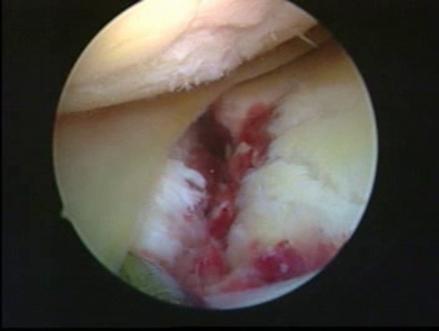

Fig. 1.13. Imagini artroscopice - leziuni osteocondrale stadiu III B si C ICRS la nivelul condilului femural si la nivelul patelei |

Fig. 1.14. Imagini artroscopice - leziuni osteocondrale stadiu IV A si B ICRS la nivelul condilului femural |